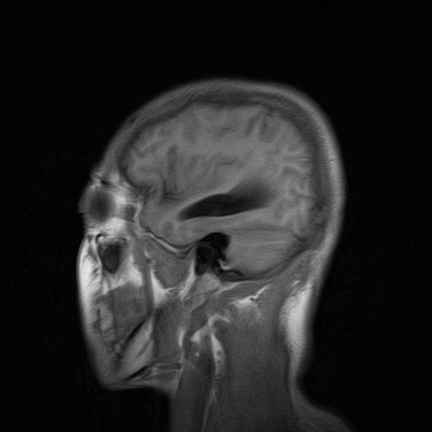

标题: MRI2064:少见病例。男性52,视力下降多年。 [打印本页]

标题: MRI2064:少见病例。男性52,视力下降多年。

四脑室区见混杂信号占位影,脑室系统扩张明显,临近结构显著受压称位,患者52岁,多考虑室管膜瘤可能性大

考虑第四脑室室管膜瘤并阻塞性脑积水。

考虑第四脑室室管膜瘤并梗阻性脑积水;部分性空蝶鞍;左侧上颌窦粘膜下囊肿。

考虑第四脑室室管膜瘤【血供丰富血管母细胞瘤可能】并梗阻性脑积水;部分性空蝶鞍;左侧上颌窦粘膜下囊肿。

比较典型的脉络丛乳头状瘤并脑积水,鉴别小脑蚓部血管母细胞瘤。